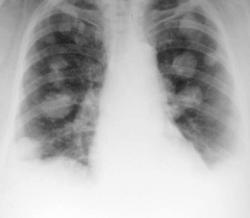

Метастазы. Наблюдение Владимира Борисовича Серова.

Метастазы. Наблюдение Владимира Борисовича Серова.

Множественные метастазы.